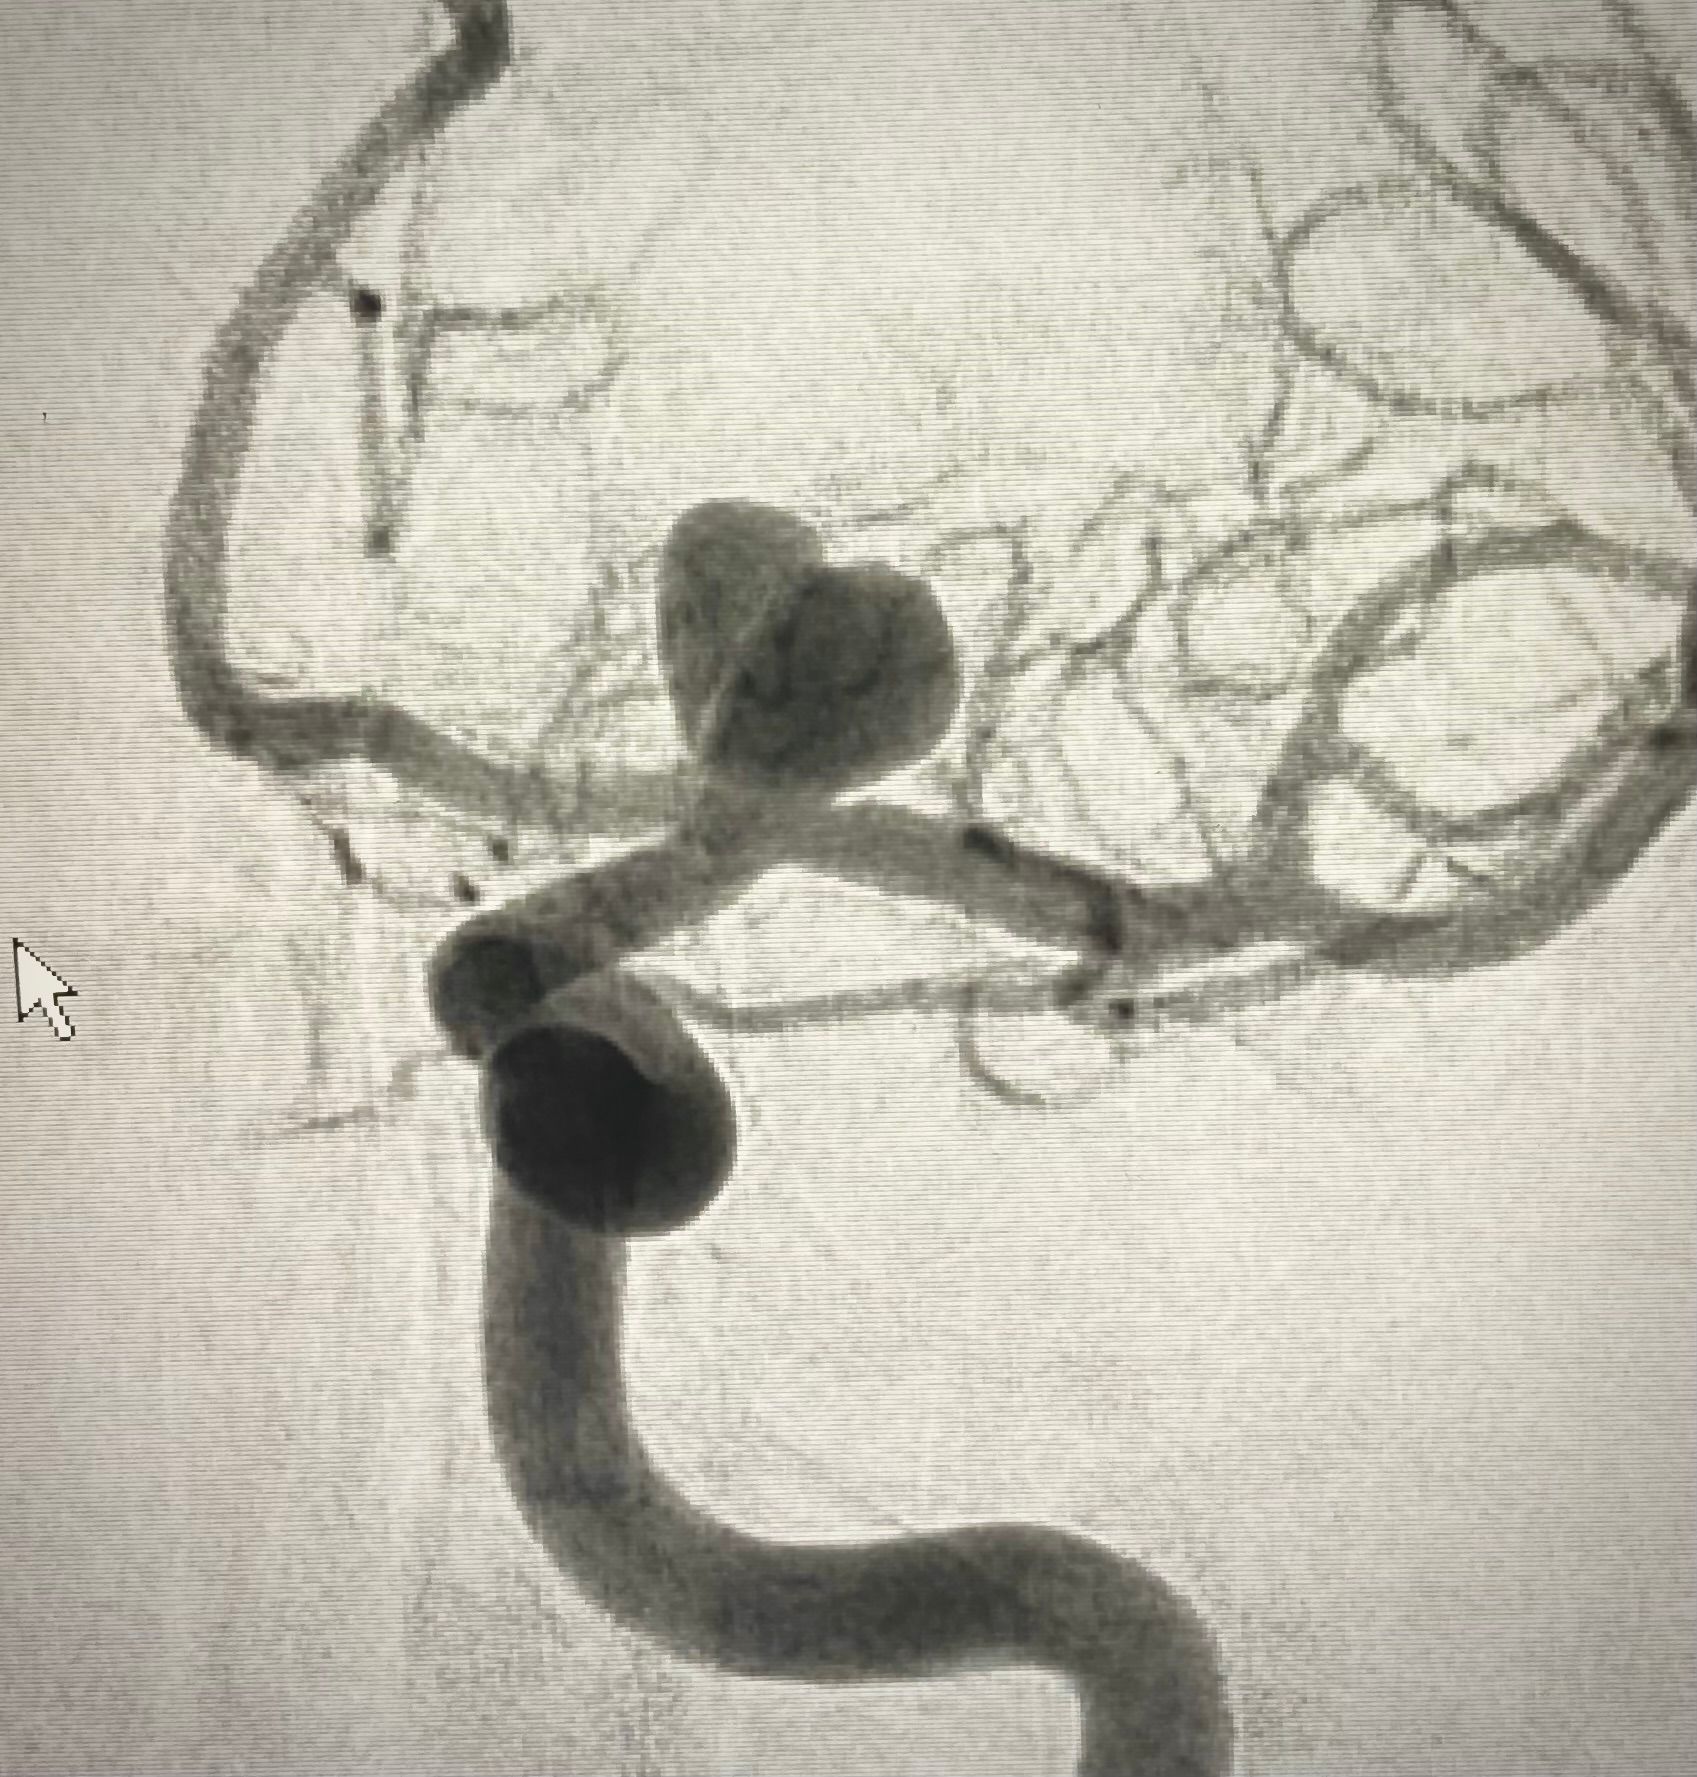

צנתורי מוח

בעל נסיון רב שנים באבחון וטיפול בפתולוגיות הקשורות לכלי הדם במוח, צוואר ועמוד השדרה.

צנתורי מוח ועמוד שדרה

ייעוץ בתחום צנתורי מוח ועמוד השדרה.